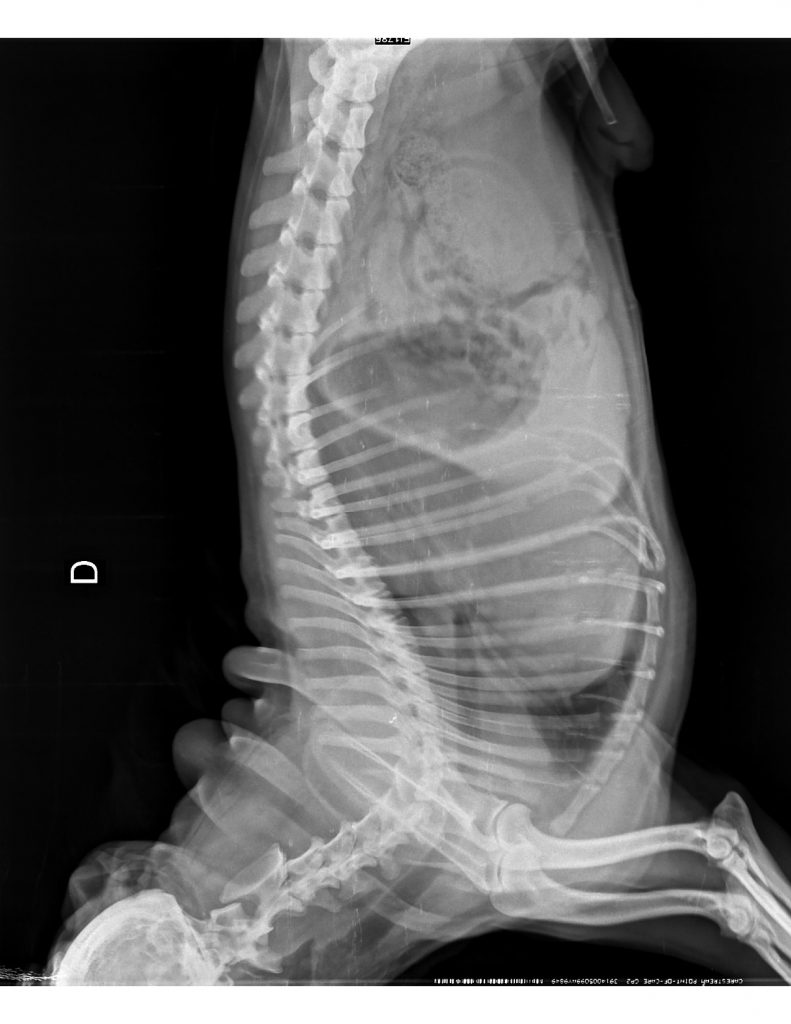

Ingresa a consulta un paciente macho canino con distress respiratorio. Los tutores indican que respira de ese modo hace semanas y que presentó pneumonia diagnosticada en otro centro veterinario hace 6 meses.

Se obtiene radiografía L-L y V-D de tórax:

Foto 2.